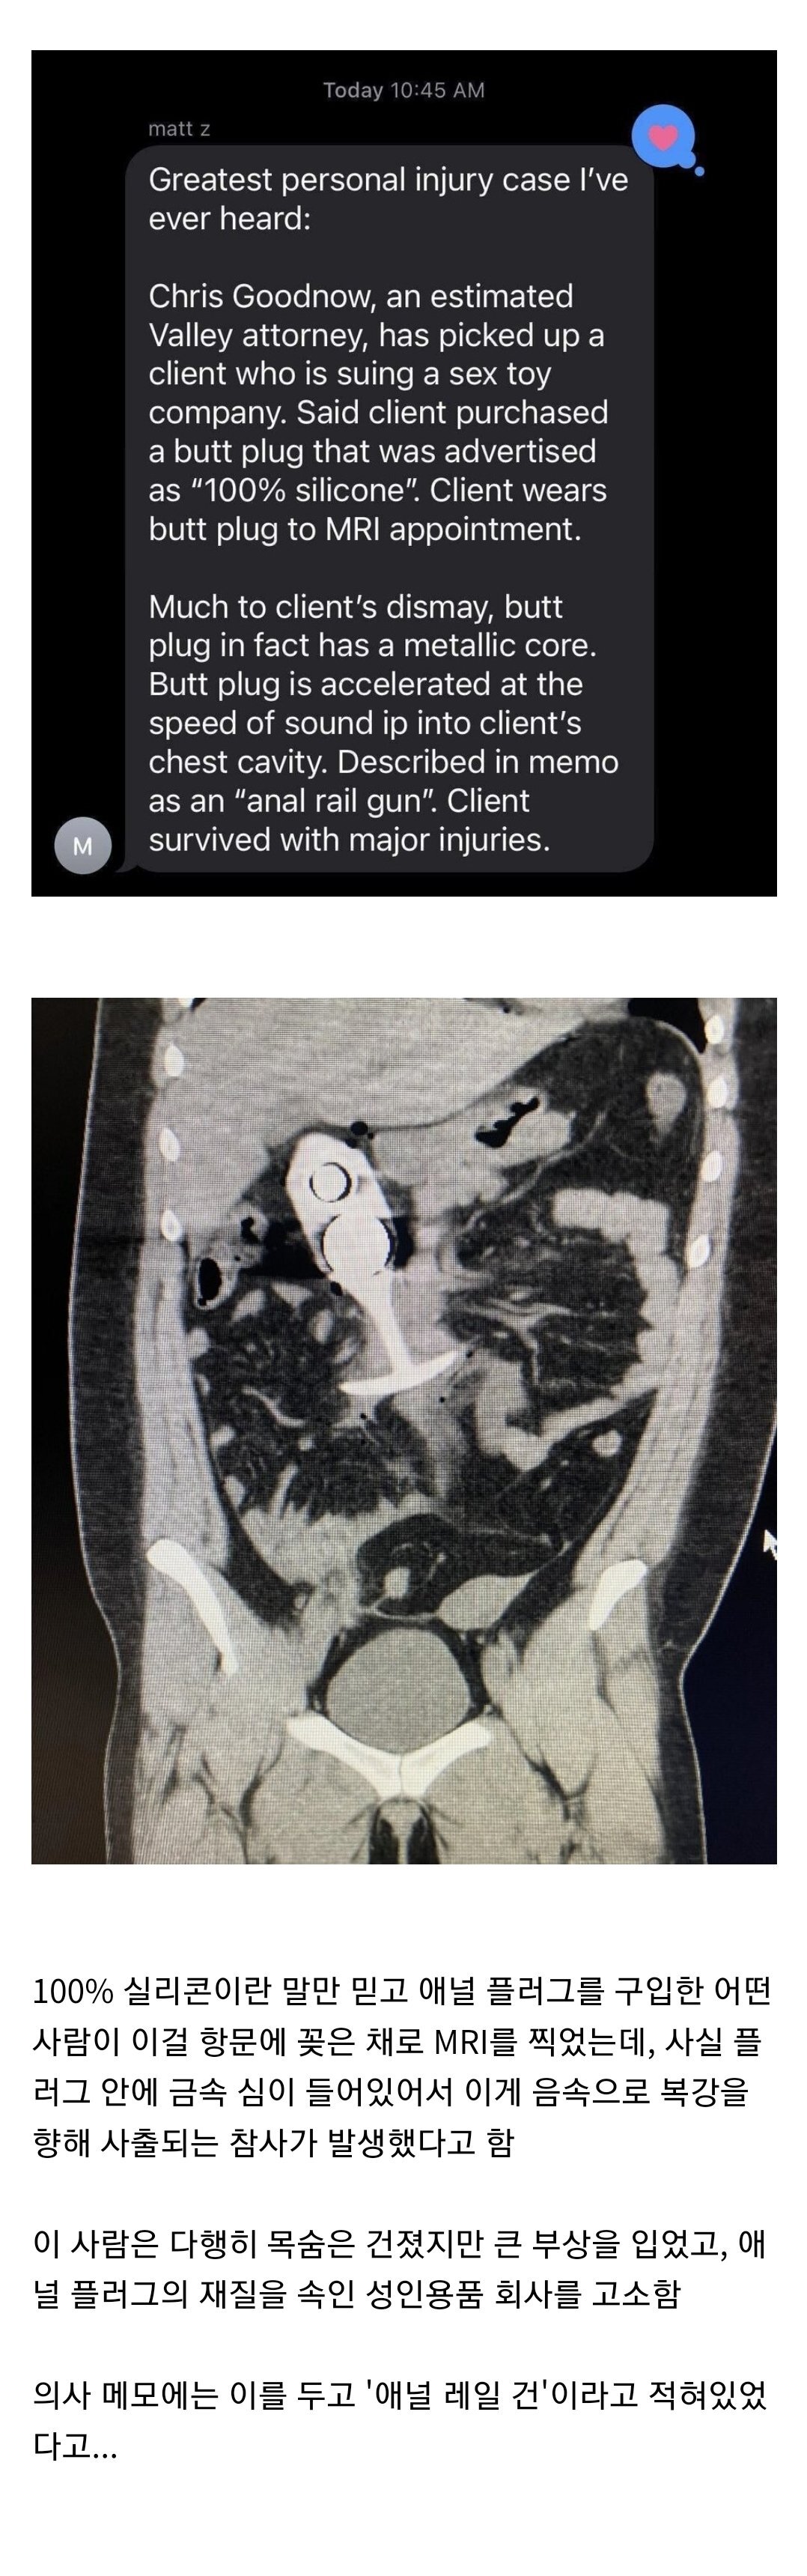

[스크랩] [놀라운 세상]공포의 애널 레일건 사건